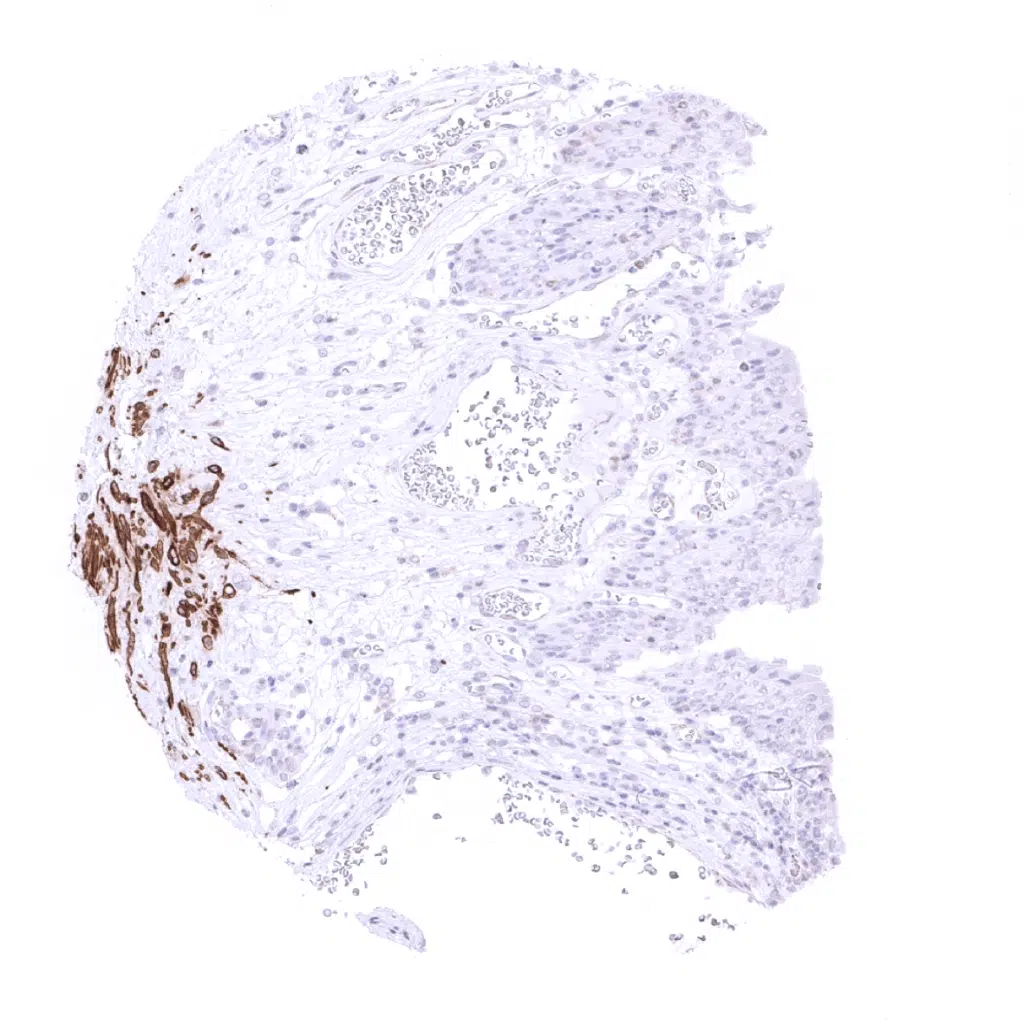

Desmin antibody [MSVA-651M] HistoMAX

Skin